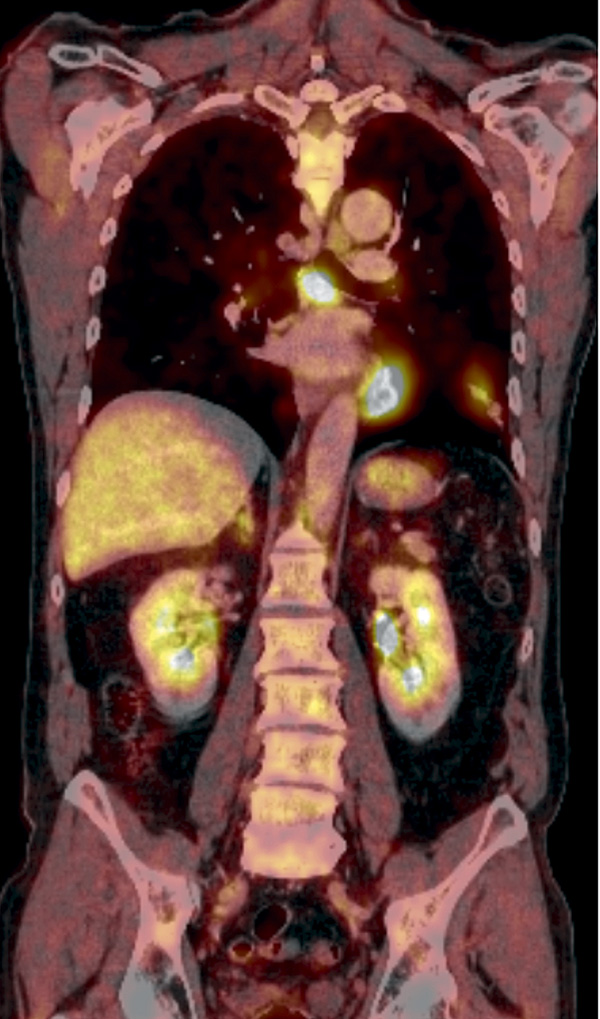

Figur 2B. Koronart snitt från PET/DT med FDG som visar spårämnesupptag i lungförtätningen och massivt upptag i mediastinala lymfkörtlar.

Fallet rör en tidigare frisk 69-årig man som aldrig hade rökt  och som insjuknade i övre luftvägsinfektion med besvärlig hosta. Husläkarens penicillin hade ingen effekt och därför beställdes lungröntgen och datortomografi, som utfördes en månad efter insjuknandet (Figur 2). Undersökningarna visade ett infiltrat basalt i vänster ovanlob, och patienten remitterades för misstänkt lungcancer. PET/DT med FDG visade spårämnesupptag i lunginfiltratet samt förstorade körtlar i lunghilus och para-aortalt med ökat upptag. Vid bronkoskopi fann man en kraftig inflammation, och PAD visade en nekrotiserande inflammatorisk process med granulom.

Det visade sig att patienten två veckor före insjuknandet hade övernattat i en sommarstuga där han först hade rensat efter vinterns musinvasion. Serologi visade tularemi. Rönt-genundersökning två månader senare visade normaliserad bild.